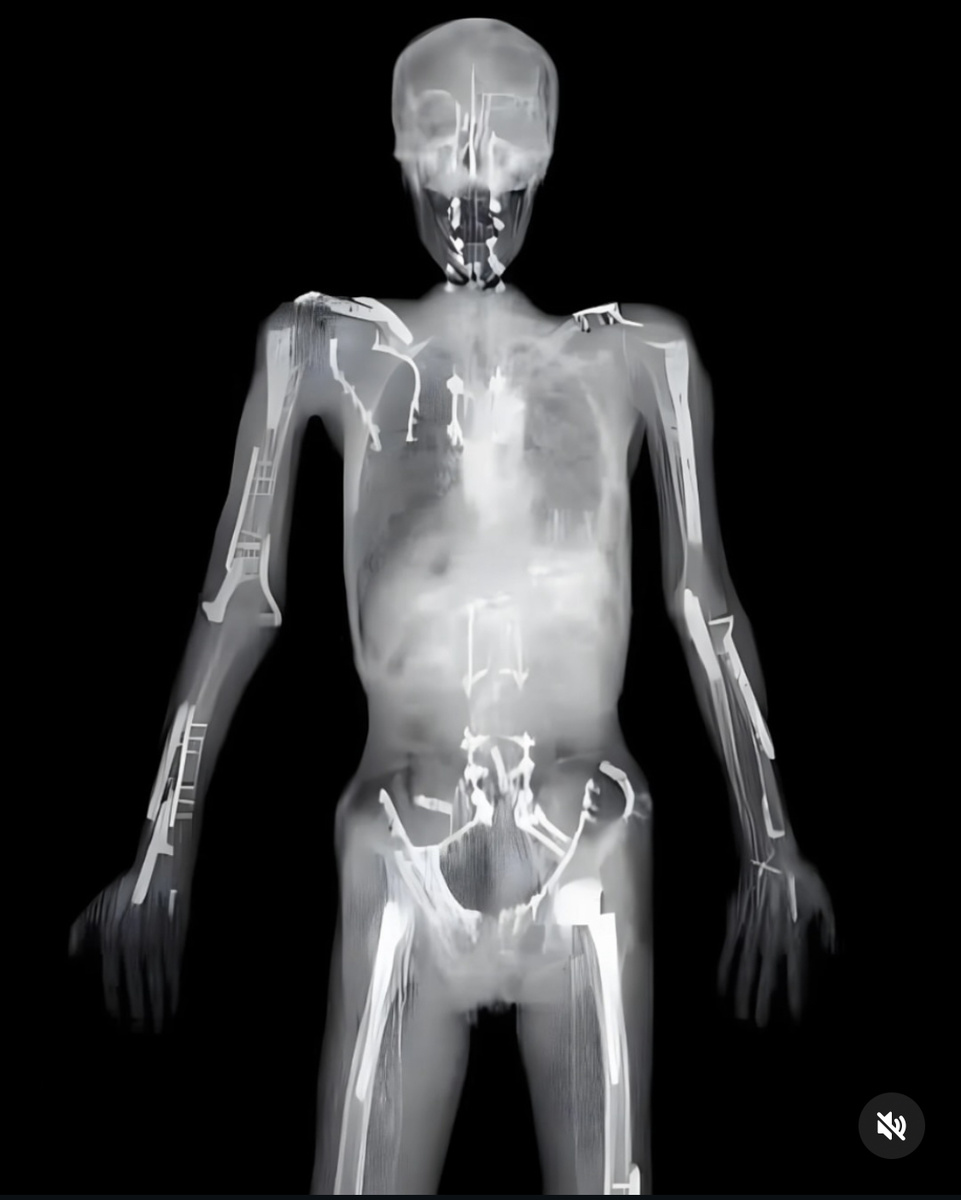

Есть известный мотоциклист, шоумэн, который перенёс бесчисленное число травм, металла в нём - килограммов пять, не меньше:

И это еще не всё, ниже есть еще железки ))) Травмы - одна хлеще другой, все высокоэнергетические, многие - смертельно опасные. Но нет, дальше - больше. Показательно, что на каждую травму у нас есть адекватный ответ. Может, это и вдохновляет на очередные «подвиги»? Мол, всё равно спасут, вылечат, не дадут пропасть!